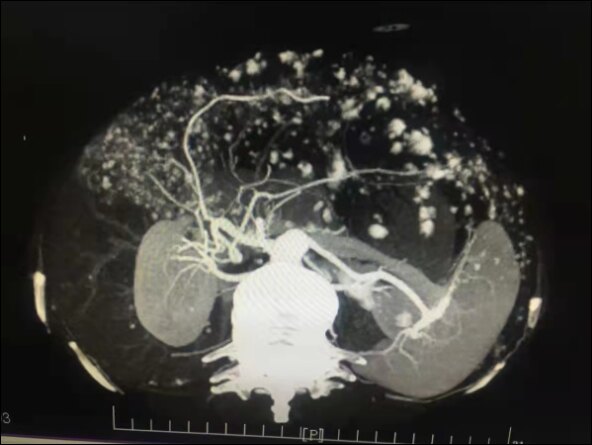

肝海绵状血管瘤,常见于中年病人。多数为单发,也可多发,肝血管瘤在肝右叶比左叶更常见,肿瘤生长缓慢,病程可长达数年以上。瘤体较小时无任何临床症状,增大后主要表现在压迫周围器官,引起上腹部不适。治疗,手术切除是最有效的方法,也可以采取介入栓塞或微波消融的方法。

此患者左肝巨大血管瘤,压迫周围组织,严重影响日常生活,在完善相关术前评估后行扩大左半肝切除。显露采用上腹部倒T切口,控制入肝血流,保留肝中静脉的右侧支,采用CUSA离断肝脏,手术顺利完成。